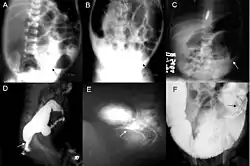

A: Plain abdominal radiograph showing a PARTZ at rectosigmoid, arrow. B: Plain abdominal radiograph showing a PARTZ at midsigmoid, arrow. C: Plain abdominal radiograph showing a PARTZ at descending colon, arrow. D: Contrast enema showing a CETZ at rectosigmoid, arrow. E: Contrast enema showing a CETZ at midsigmoid, arrow. F: Contrast enema showing a CETZ at descending colon, arrow.

Radiologic findings may also assist with diagnosis.[33] An abdominal x-ray can reveal a lack of stool in the large intestine or a bulging caused by blocked stool.[34] Cineanography (fluoroscopy of contrast medium passing anorectal region) assists in determining the level of the affected intestines.[35]